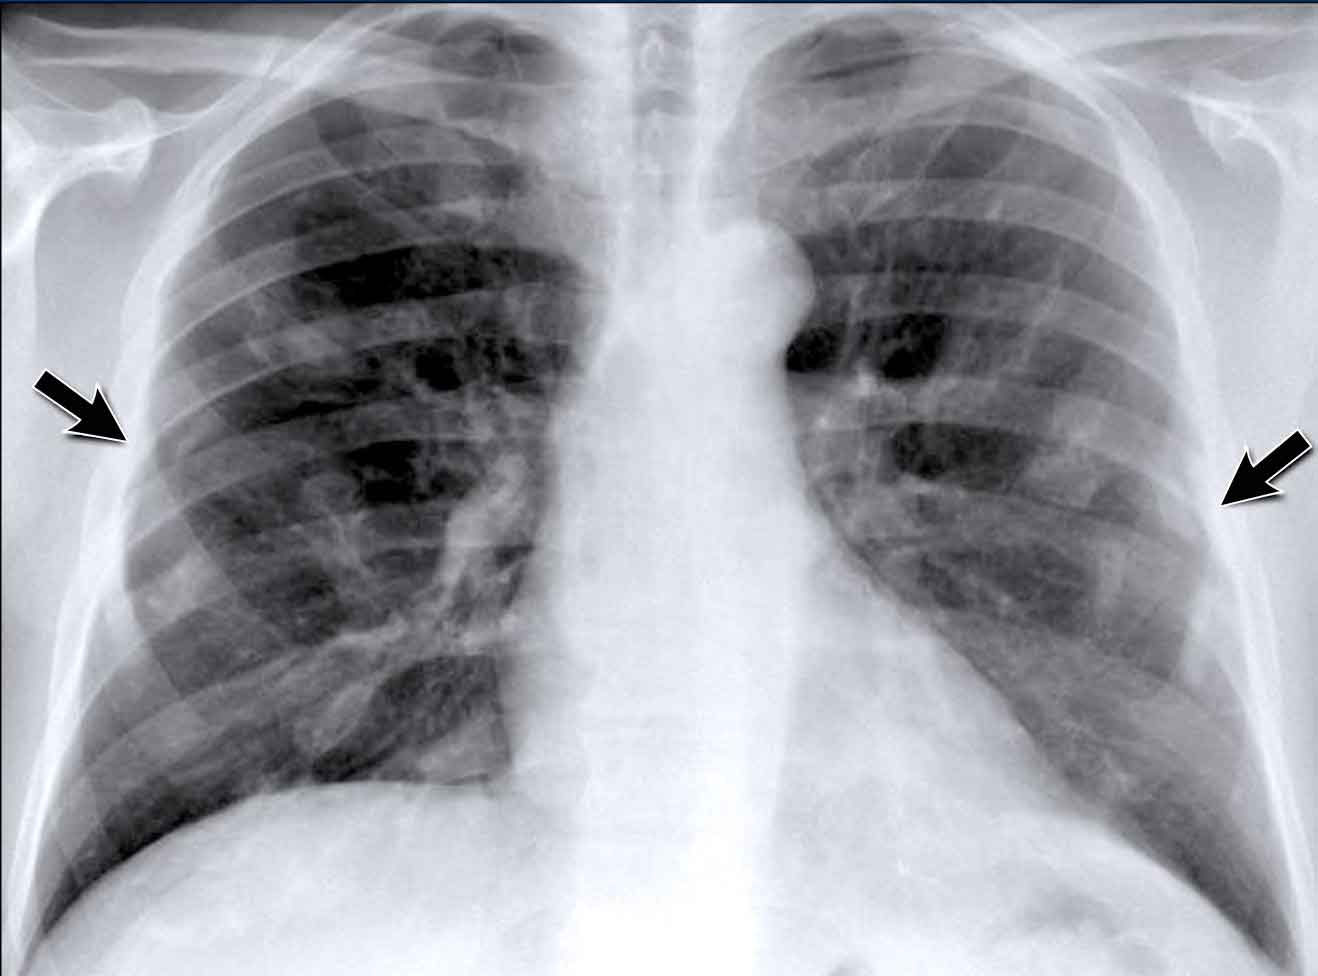

Pleural Plaques (Asbestos-Related)

- Multiple irregular pleural opacities are seen.

- Some follow the contours of the chest wall (arrows).

- Typical features of asbestos-related pleural plaques:- Bilateral, extensive

- Often involve the diaphragmatic domes

Unilateral calcified pleural opacities may indicate: